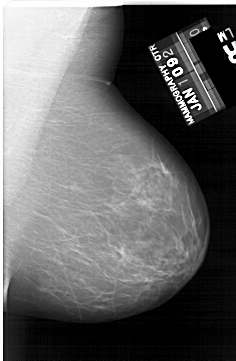

A_1634_1.RIGHT_CC

RIGHT_CC LINES 5791 PIXELS_PER_LINE 3901 BITS_PER_PIXEL 12 RESOLUTION 43.5 NON_OVERLAY